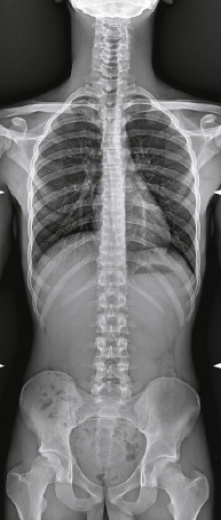

- Различные режимы съемки: рентгенография, рентгеноскопия, линейная томография, томосинтез, сшивка